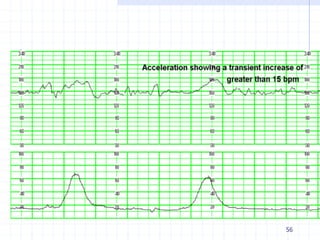

Acceleration

An abrupt increase in the FHR.

 Before 32 weeks of gestation, accelerations should last

≥10 sec and peak ≥10 bpm above baseline.

 After 32 weeks gestation, accelerations should

last ≥15 sec and peak ≥15 bpm above baseline.

A prolonged acceleration is ≥2 minutes but less

than 10 minutes. An acceleration of 10 minutes or

more is considered a change in baseline

Physiologic response to fetal movement

56